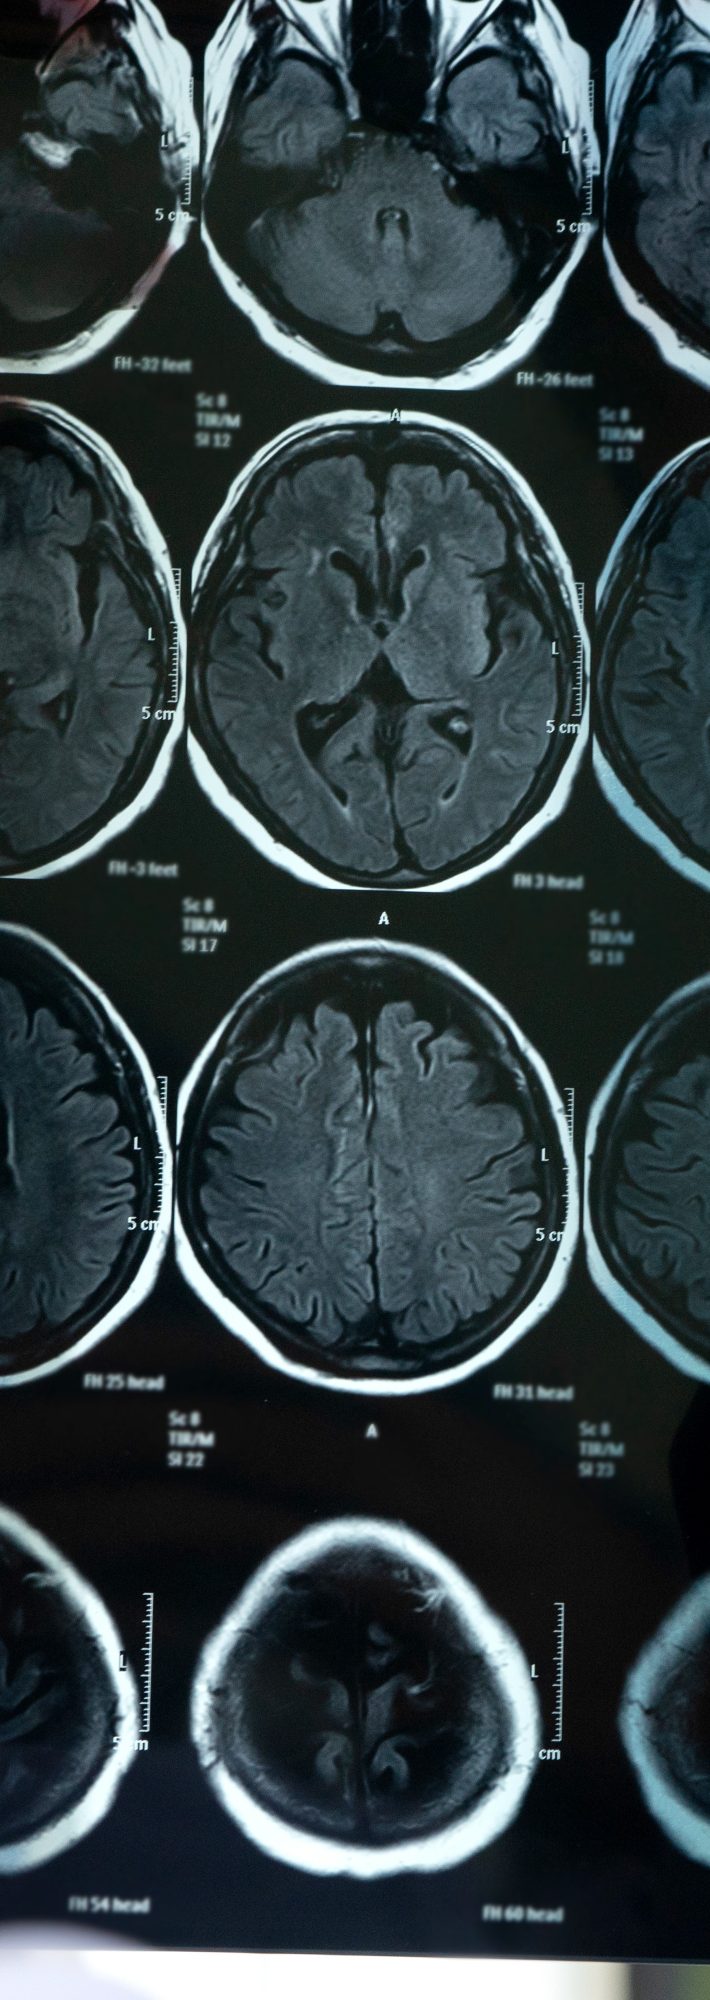

脳梗塞で倒れた夫にがんまで発覚。病室で“夫の切ない一言”に号泣

脳梗塞の原因が判明、告げられた病名は…